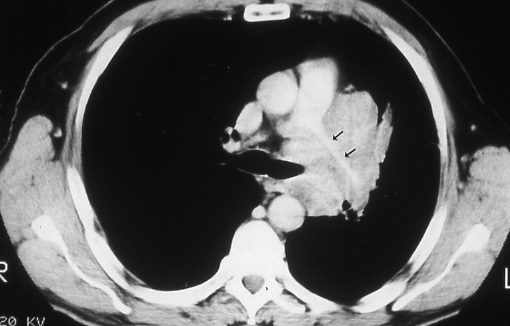

Fig. 21: Computed tomographic scan of the chest showing an extensive cancer in the left lung extending into the mediastinum, pericardium, and compressing the left pulmonary artery (black arrows), T4.